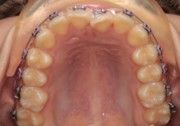

The right side shows a wide, clean bend with no distortion and minimal extra wire while bending with the IOS Mini Cinch Back Plier.

Both sides exhibit ideal bends when bent with the IOS Mini Cinch Back Plier.

The left side shows a near-perfect 90° bend, created with maximum force using the IOS Mini Cinch Back Plier (not necessary, but Dr. Nielson wanted to test the upper limit).

Again, ideal bends were made very close to the bracket with the IOS Mini Cinch Back Plier, with no risk of dislodgement.